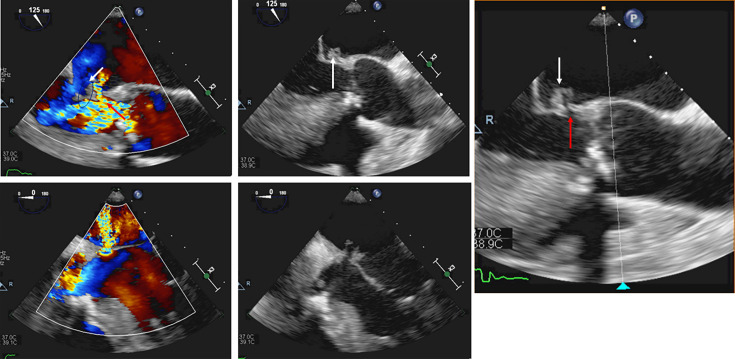

Background. Aerococcus urinae was initially considered a commensal of the urinary tract, but there is now increasing evidence for its involvement in urinary tract and systemic infections. A. urinae endocarditis has a non-negligible mortality rate and occurs mainly in patients with underlying conditions or the presence of extraneous material. Case presentation. This report handles the case of a 65-year-old male with cardiac antecedents, who was admitted to the cardiology department after a syncope of unknown origin and diagnosed with severe mixed aortic valve disease and mitral valve sclerosis through the means of transoesophageal echocardiography (TEE). During hospitalization, the patient progressively deteriorated with the development of shortness of breath and an inflammatory syndrome. Both the urine and blood cultures showed growth of A. urinae. Treatment with piperacillin/tazobactam was started empirically. Repeated TEE showed evidence of endocarditis with vegetation and perforation of the mitral valve that required an emergency surgery with mitral valve repair. After surgery, gentamicin and penicillin G were administered for 48 h, followed by combined ceftriaxone/penicillin G treatment for 6 weeks. At first, flucloxacillin was also associated as the culture of the valve was negative. Finally, the 16S rRNA gene PCR on the valve tissue confirmed the A. urinae endocarditis. Conclusion. A. urinae is an underestimated cause of serious infections such as endocarditis. Urinary tract infections mainly in older men can be an entry point for this type of invasive infection.